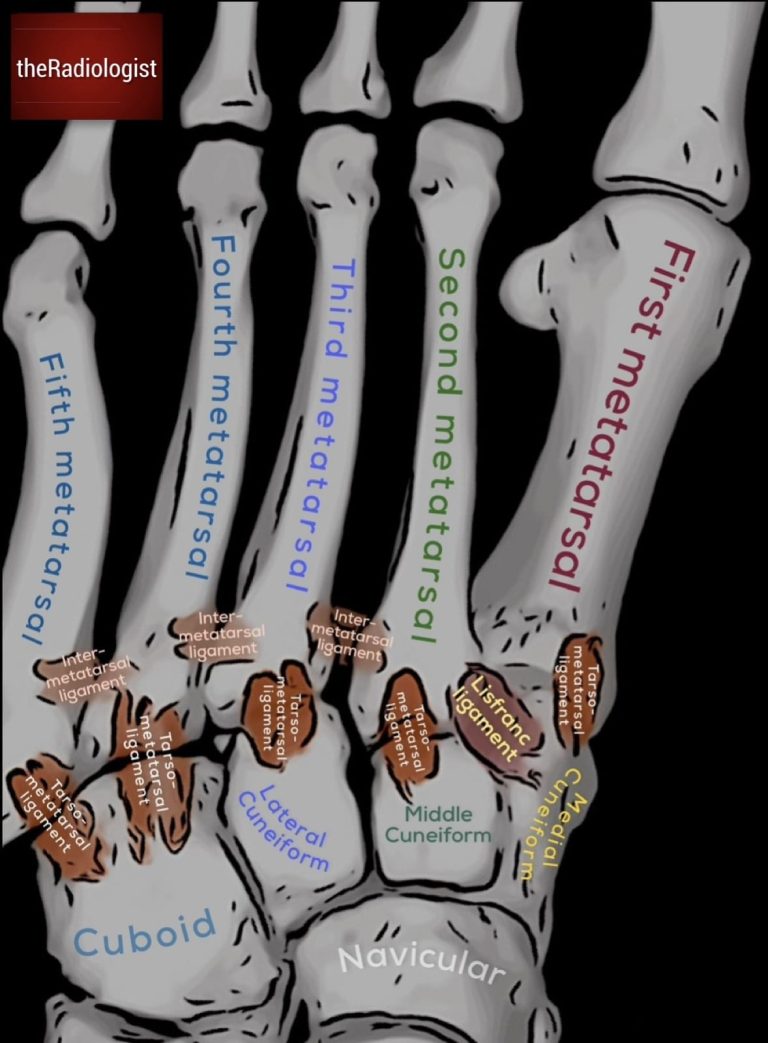

The LisFranc joint complex holds together the metatarsal and tarsal bones – it includes the tarsometatarsal ligaments and intermetatarsal ligaments as well as the LisFranc ligament which holds together the medial cuneiform and 2nd metatarsal.

The LisFranc joint complex holds together the tarsal and metatarsal bones. The LisFranc ligament holds together the medial cuneiform and the second metatarsal.

• Lisfranc joint: the whole tarsometatarsal complex.

• Lisfranc ligament: the band from the medial cuneiform to the 2nd metatarsal base.

• Lisfranc injury: fracture-dislocation at the tarsometatarsal joint.

• Lisfranc fracture: when there is an associated fracture (though injury may be purely ligamentous).